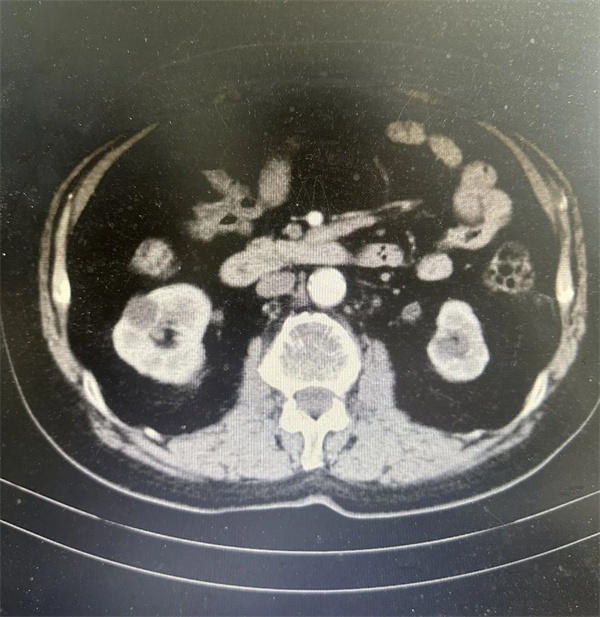

老先生因突然发现不明原因的无疼痛感尿血,前往峨眉山佛光医院泌尿外科就诊。经过尿常规和中下腹部CT等系列检查后,医院专家团队发现老先生右侧肾盂存在肿瘤迹象,同时排除了其他潜在疾病。